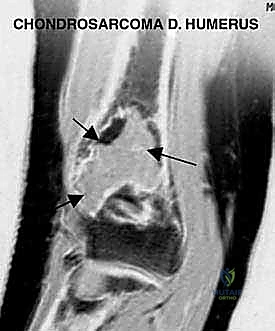

- الساركوما الغضروفية (Chondrosarcoma):

- ينشأ هذا الورم من الخلايا الغضروفية.

- يصيب عادة البالغين وكبار السن (فوق 40 عاماً).

- لا يستجيب جيداً للعلاج الكيميائي أو الإشعاعي، مما يجعل الاستئصال الجراحي الواسع (الذي يبرع فيه د. هطيف) هو العلاج الأساسي والوحيد للشفاء.

- التصوير بالرنين المغناطيسي (MRI): هو المعيار الذهبي. يوضح بدقة متناهية امتداد الورم داخل نخاع العظم، وحجم الكتلة الورمية في الأنسجة الرخوة المحيطة (العضلات)، ومدى قرب الورم من الأعصاب والشرايين الرئيسية.

- التصوير المقطعي المحوسب (CT Scan): يساعد في التخطيط الجراحي ثلاثي الأبعاد وتقييم التدمير العظمي القشري.